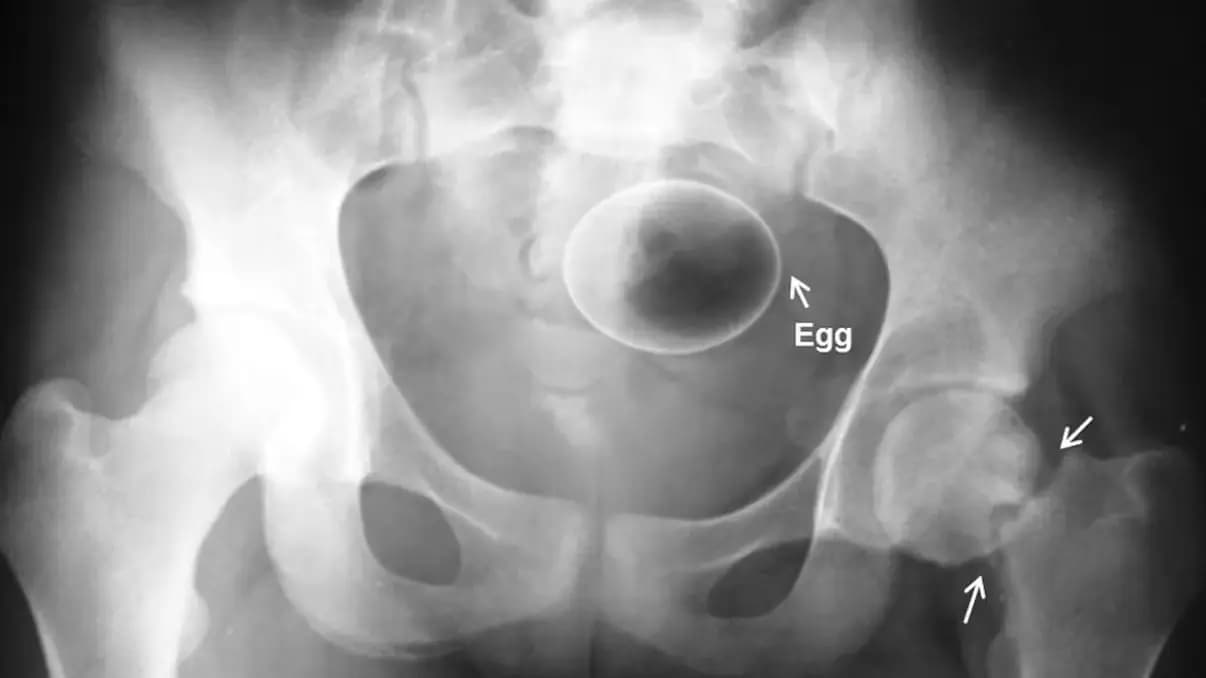

25 предметов, которые не должны быть внутри вас: рейтинг от врачей скорой помощи